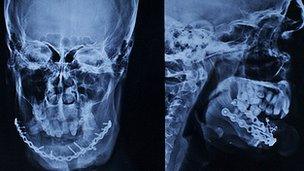

The 12-year-old walks on a prosthetic leg and still has no upper teeth, but his face is being painstakingly rebuilt. In one extremely complicated operation, rarely performed anywhere in the world, a muscle from his back was transferred to his mouth to help rebuild his lip.